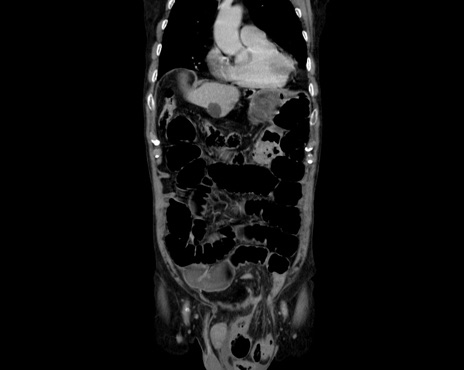

症例26(冠状断像)

【症例】80歳代男性

【主訴】嘔吐

【現病歴】昨晩2回嘔吐あり、今朝になっても嘔吐あり。来院。

【既往歴】胃潰瘍

【身体所見】意識清明、BT 37.6℃、BP 166/95mmHg、HR 100bpm、SpO2 97%、腹部:平坦・軟、腸蠕動音聴取良好、圧痛なし。

【データ】WBC 21900、CRP 1.4